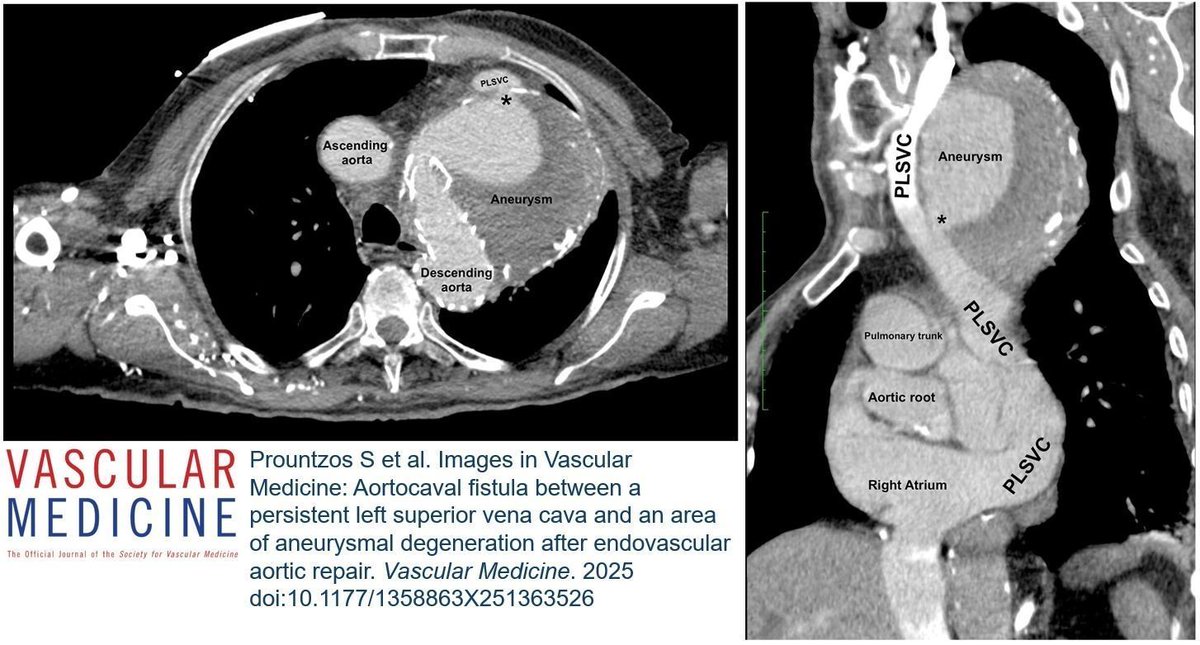

From the latest issue: Yamada and colleagues report the prevalence of calcified nodules in patients with carotid artery stenosis and study their association with clinical outcomes. https://t.co/aBG6wJe3MZ

#CarotidStenosis